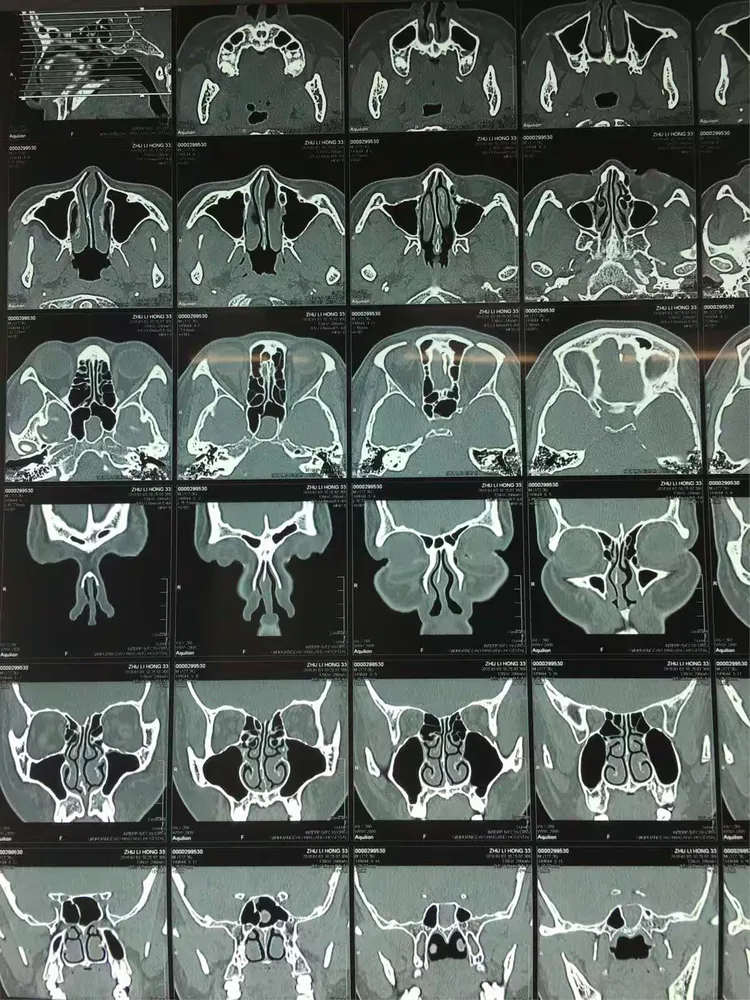

既往史:慢性鼻窦炎病史,04